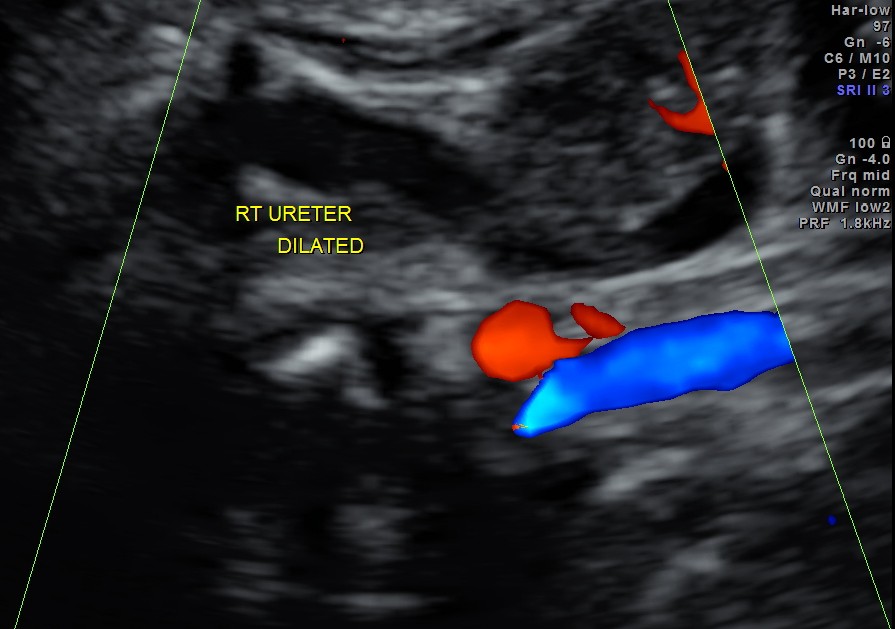

Rt proximal ureter is mildly dilated

Right sided hydro uretero nephrosis , with likely obstruction at right vesico ureteric junction.